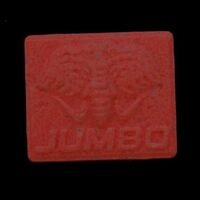

Baza tabletek Ecstasy zawiera analizy laboratoriów i użytkowników. Wyniki to ostrzeżenia. Żadna substancja nie jest w 100% bezpieczna. Badaj substancje przed zażyciem. Sprawdź narkotest.

Zastrzeżenie: Informacje przedstawione na tej stronie nie mają na celu promocji zażywania narkotyków. Wiele wymienionych substancji jest nielegalne według prawa krajowego i międzynarodowego, posiadanie tych substancji jest karane przez prawo. Nigdy nie zakładaj, że substancja jest bezpieczna. Tabletki Ecstasy (extasy, XTC, emka, molly) powinny zawierać MDMA ale stężenie, czystość i domieszki bardzo się różnią, nawet jeśli próbki pochodzą z tego samego źródła lub wyglądają podobnie. Chemical Safety sp. z o.o. stanowczo odradza używania jakichkolwiek substancji psychoaktywnych – legalnych lub nielegalnych. Zażywanie substancji psychoaktywnych zawsze jest możliwym do uniknięcia ryzykiem dla zdrowia.